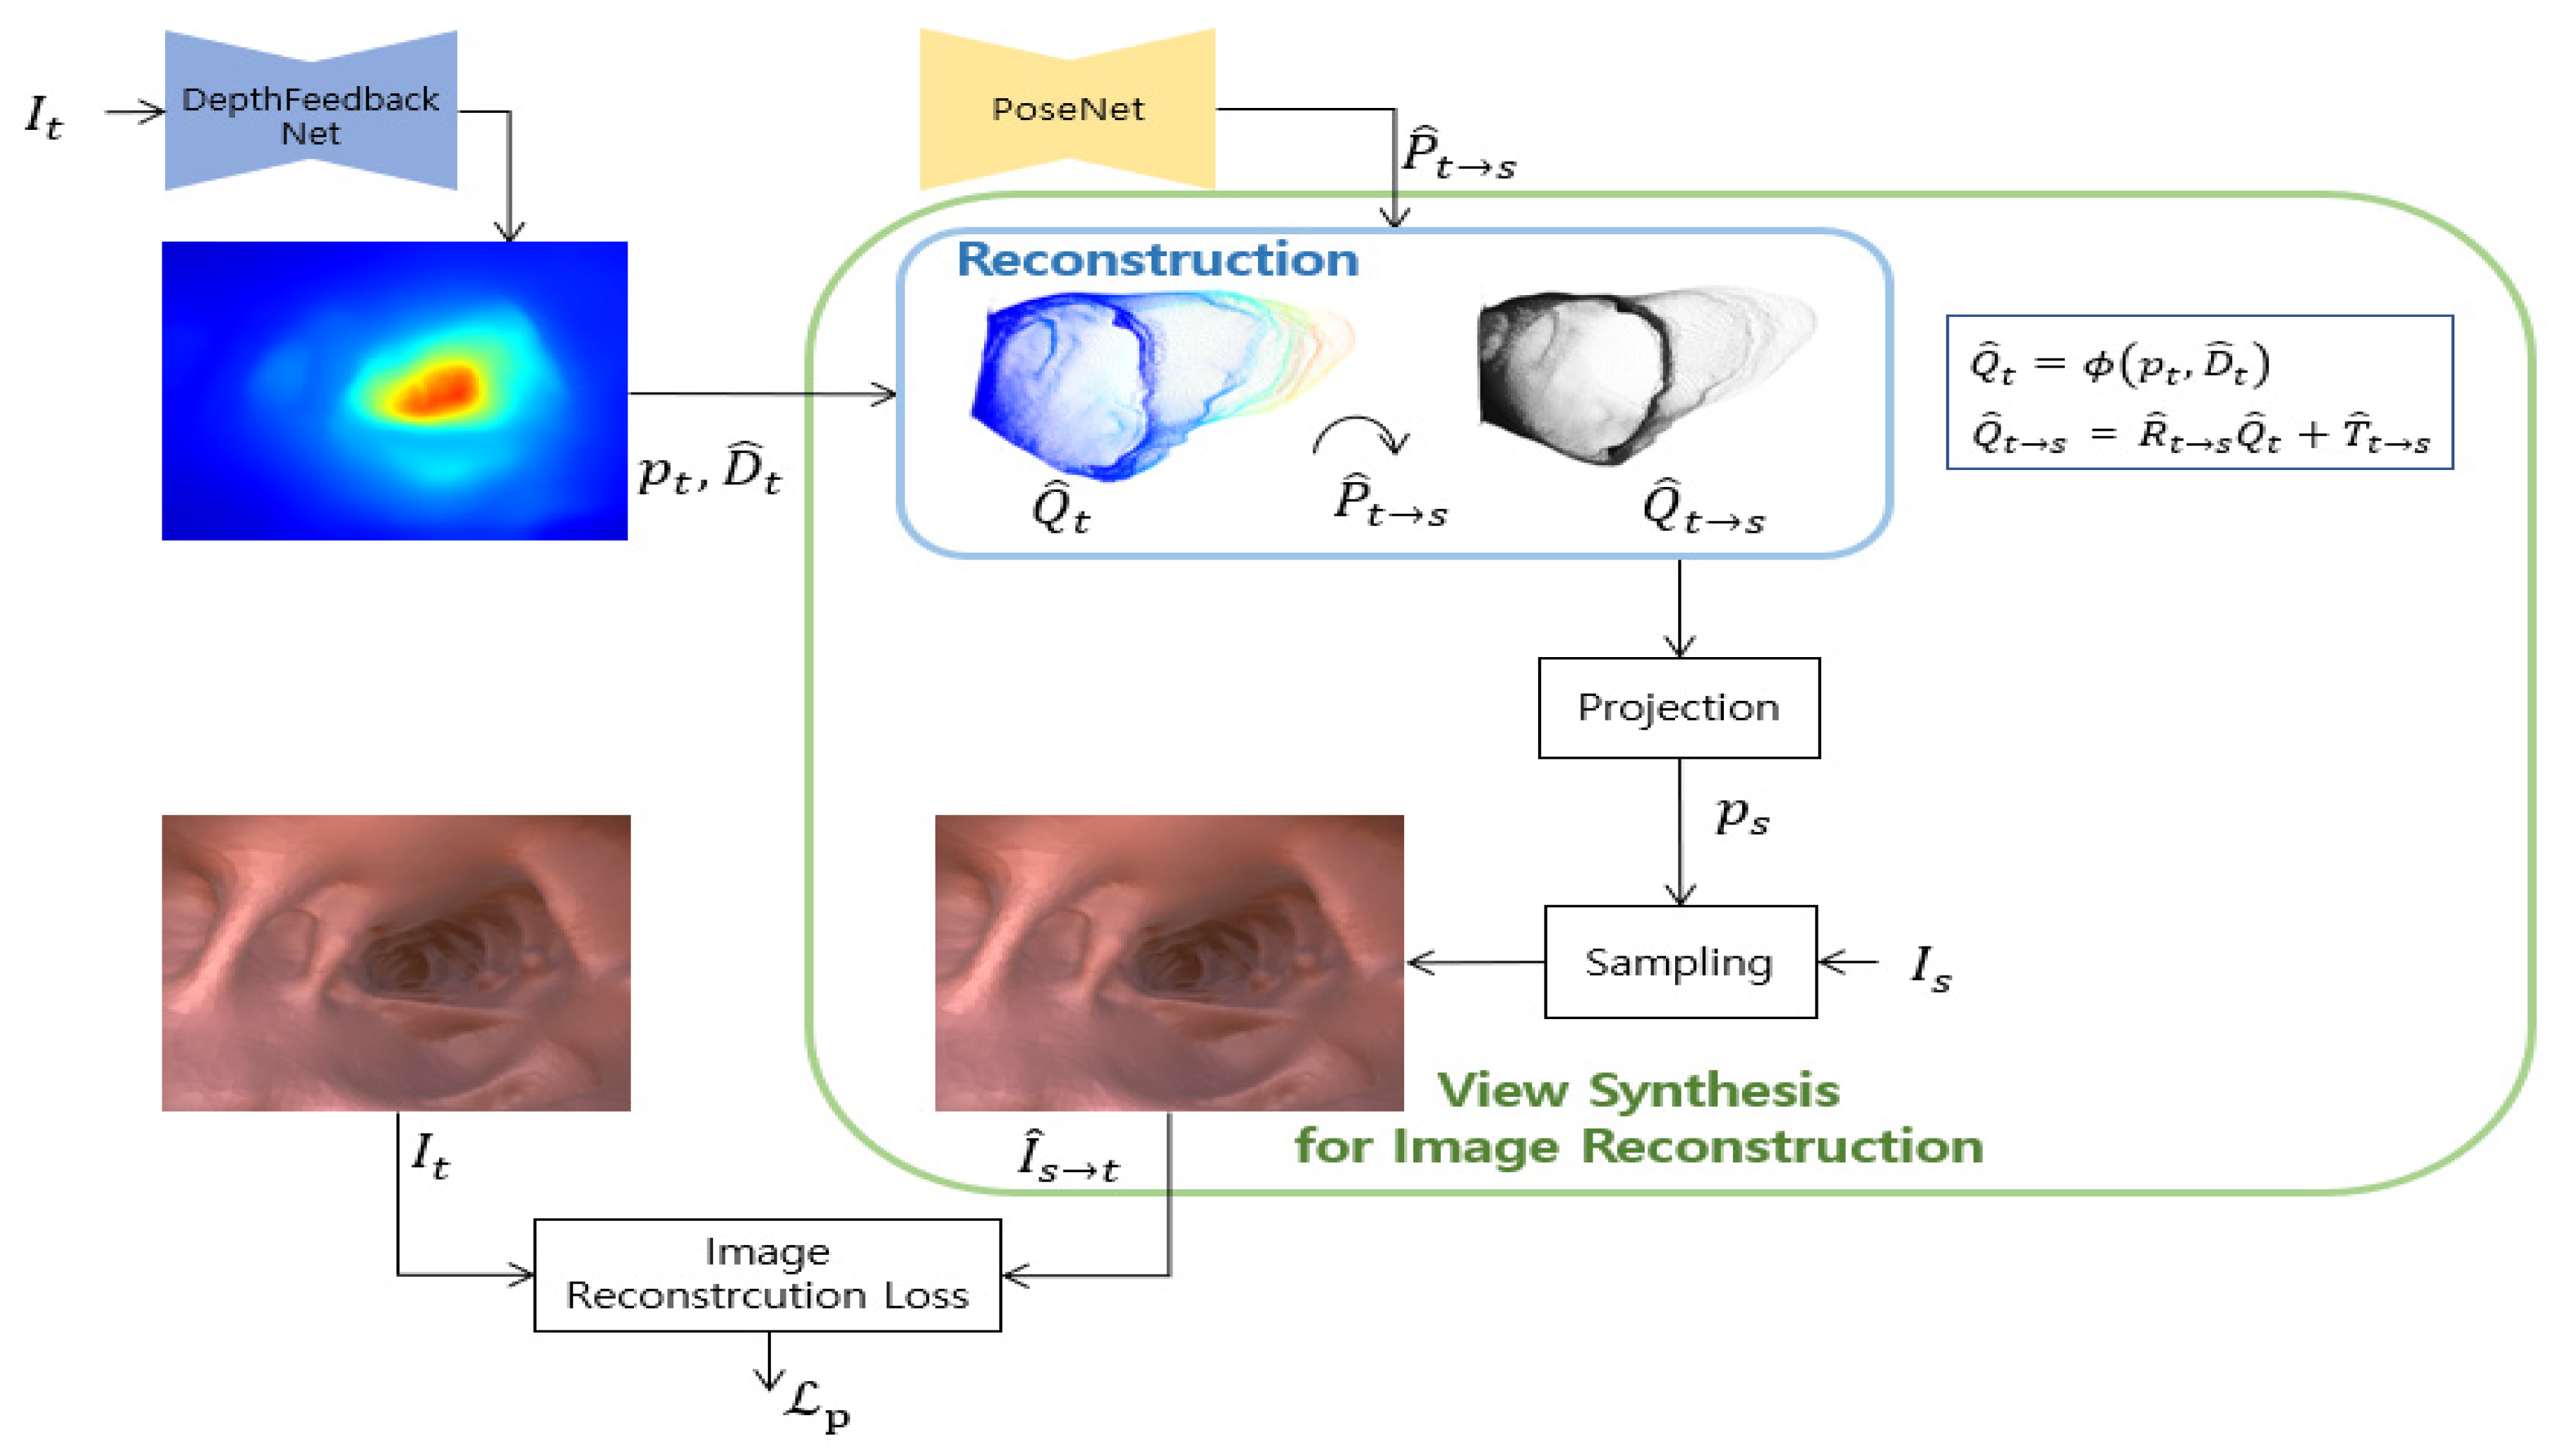

3.1.1. Image Reconstruction Loss

3.2.1. Depth Reconstruction Loss